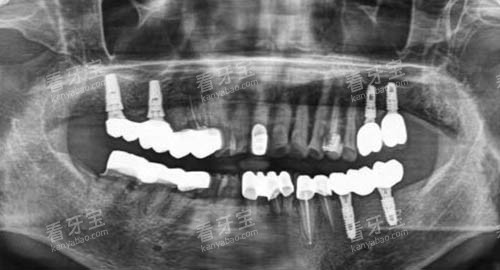

在牙齿种植方面,配备了智能化种植系统,该系统可以通过三维成像技术正确地分析患者口腔的骨骼结构、神经分布等情况,为种植方案的制定提供精密的数据支持,大大提高了种植手术的成功概率和靠谱性。

在牙齿种植方面,医院使用的种植体都是经过地区食品药品管控管理总局认证的合格产品,具有良好的生物相容性和稳定性。